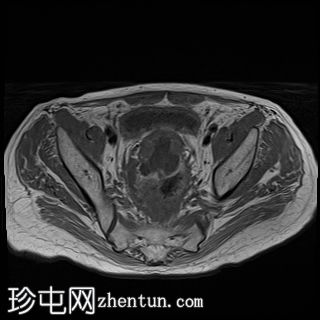

轴位

T2加权像

直肠下三分之一处可见一段弥漫性不规则肠壁增厚,伴浆膜外延伸,在右前外侧壁形成“C”形肿块,增强后呈不均匀强化,中央可见坏死。

可见少量细小的肠系膜、髂内和髂外淋巴结。